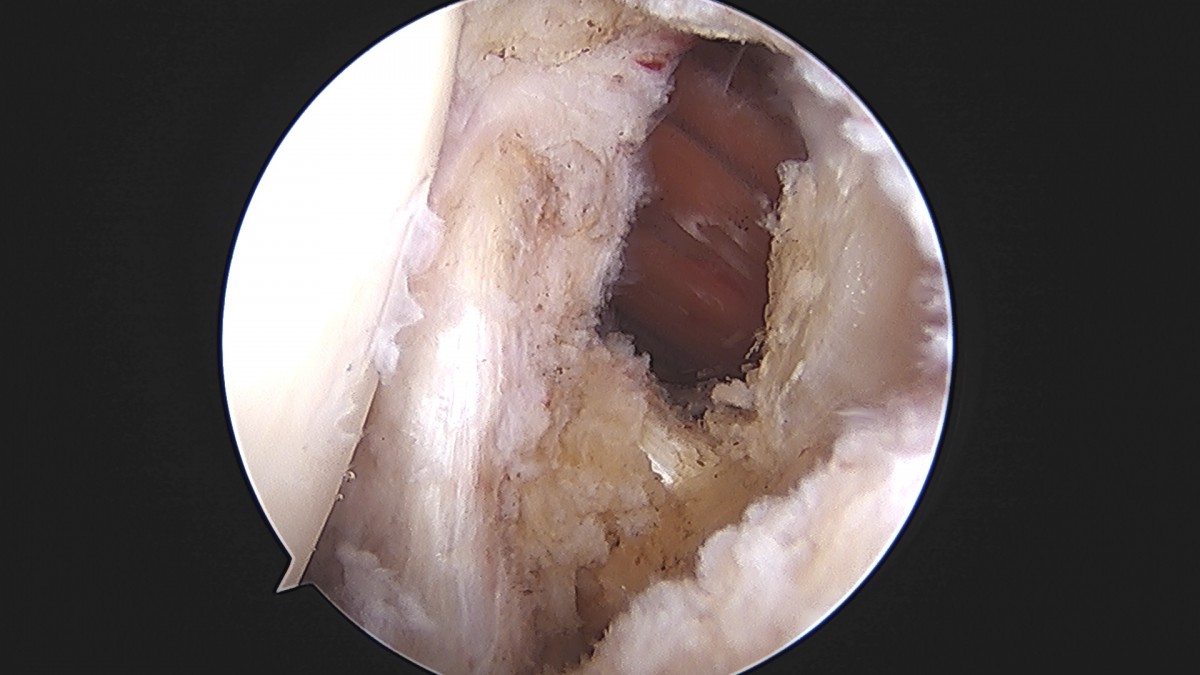

이재상원장님 어깨 견봉하 감압술 및 관절낭 이완술 주혜O 환자

dae765e4d9ac96aee867c9d6292d8784_1758003912_2111.jpg